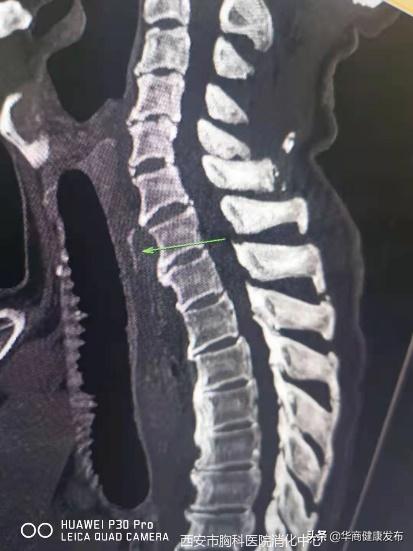

7月13日下午,西安市胸科医院消化内科门诊来了一位82岁的老人,因为进食过程不小心,一根鱼刺卡在了食管内已经超过24小时,就诊多家医院,无法取出异物。张蓉医生仔细询问了患者病情,迅速为老人完善了内镜和异物取出术的相关检查,以尽快解除险情,避免异物进一步扎穿食管,增加治疗的创伤和复杂性。

情况紧急,张蓉医生立即为老人行胃镜下异物取出术,仅用10分钟,张蓉医生用异物钳将鱼刺成功取出。老人安全返回病房,经观察没有任何不适,恢复正常进食。

鱼刺约1.5cm长,位于颈7水平,食道前壁偏右侧